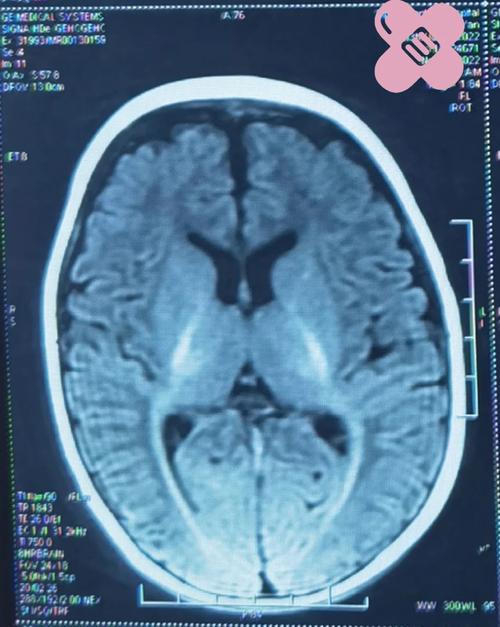

核磁共振检查新生儿脑改变有何临床意义及诊断价值?-第1张图片-郑州医学网

(图片来源网络,侵删)

新生儿正常脑部MRI的“改变”(发育特征)

在解读新生儿MRI时,首先要了解其与成人的根本区别,这些“改变”其实是正常的发育过程

1. 高信号的脑白质

• 表现:在T1加权像上,新生儿的大脑白质信号比灰质更高(更亮);在T2加权像上,白质信号则比灰质更低(更暗),这与成人正好相反。

• 原因:这是由于白质中含水量极高,且髓鞘化过程尚未开始或刚开始,髓鞘是包裹神经纤维的脂肪组织,在T1像上呈高信号,新生儿脑白质中的水分抑制了T1信号,而成人髓鞘丰富的白质则呈高信号,随着婴儿成长,髓鞘逐渐形成,白质信号会逐渐向成人模式转变。

2. 不成熟的脑沟和脑回

• 表现:脑表面光滑,沟回浅而宽,尤其是额叶和枕叶。

• 原因:大脑皮层正在快速折叠和增厚,这个过程在出生后仍持续数月。